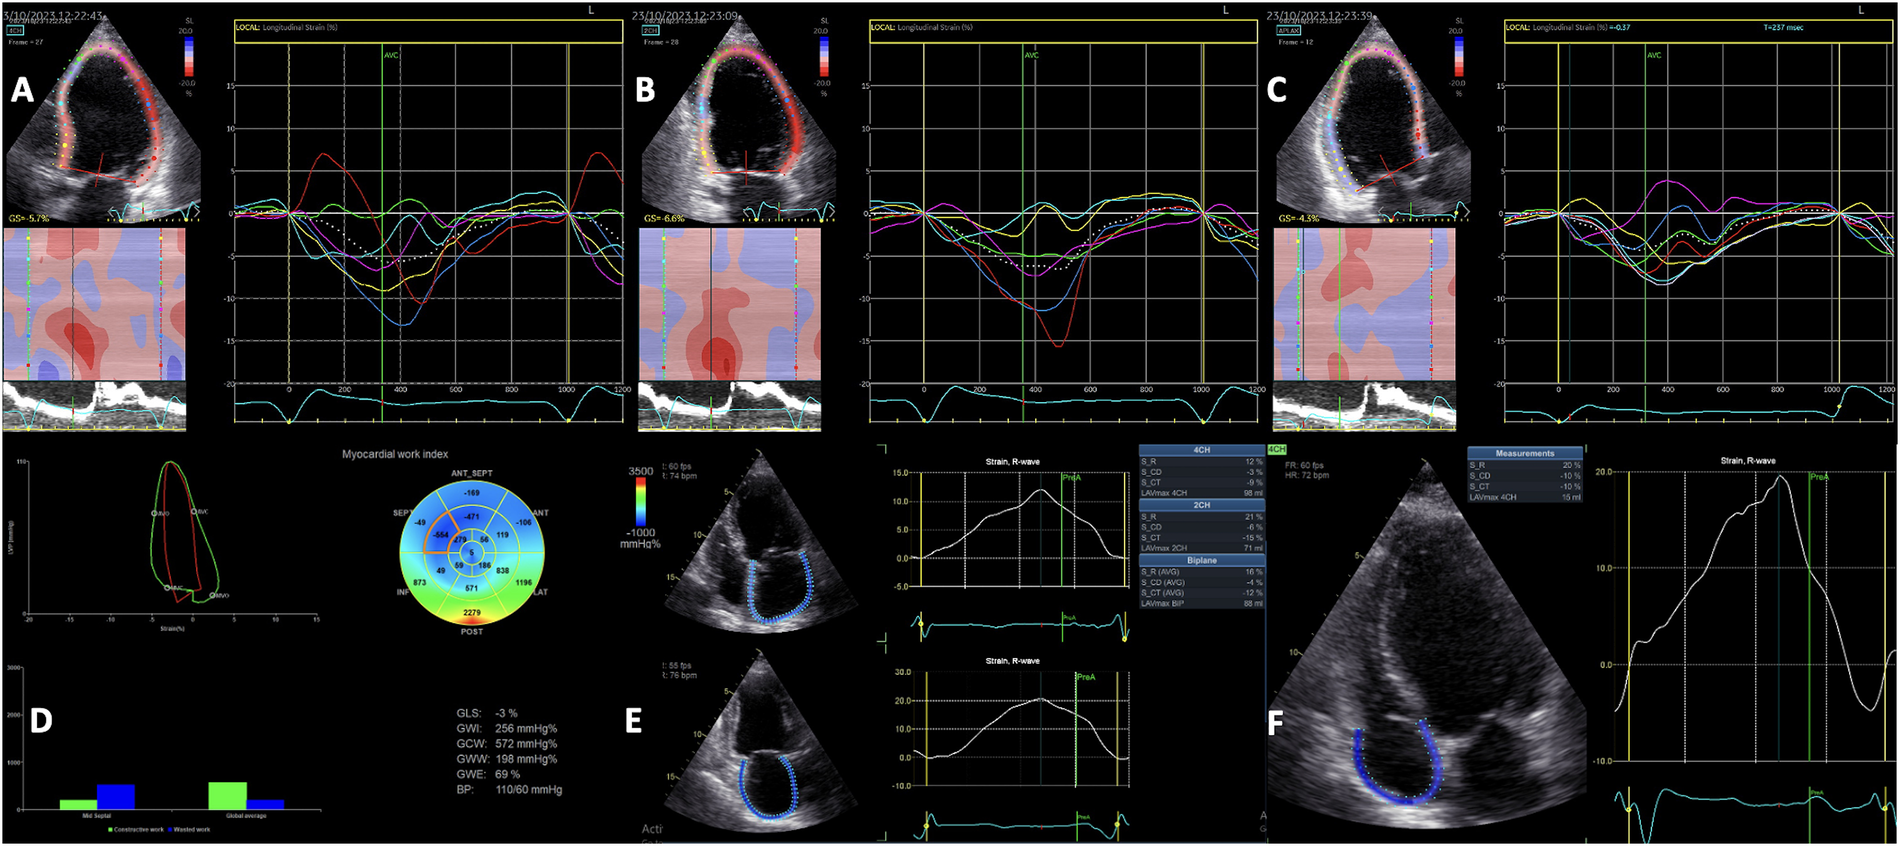

Mechanical dyssynchrony, rather than electrical dyssynchrony, serves as the primary predictor of responsiveness to CRT. On one hand, electrical dyssynchrony, evaluated by QRS duration on an ECG, may be less reliable due to scar-related moderate QRS enlargements that may not correspond to significant mechanical dyssynchrony. This phenomenon is especially noticeable among patients with an ischemic etiology of HF, in which several myocardial segments have delayed contraction, often attributed to scar tissue formation. On the other hand, scar tissue or fibrosis, resulting in reduced or lack of contractile reserve, influence CRT response. However, relying solely on time-delay indexes for identifying responders is inherently limited since it does not consider residual myocardial contraction. Accordingly, comprehensive echocardiographic evaluations of both LV mechanical dyssynchrony (Figures 2A–C) and contractile function, providing insights into myocardial viability and scar tissue burden, can now be conducted reliably and independently of imaging angles through the application of STE (75, 76). Delgado et al. proved that combining the LV radial dyssynchrony with the radial strain of the LV segment corresponding to the LV lead placement (with values <16.5% indicating a myocardial scar with >50% transmurality as validated by cardiac magnetic resonance), and placing the LV lead in the latest activated segment defined as concordant lead position predicted the long-term survival in a large cohort of ischemic HF patients (77). These three parameters provided additional prognostic value beyond that offered by clinical parameters alone. However, radial dyssynchrony cannot be used in patients with a history of septal infarction.

Figure 2

Two-dimensional speckle-tracking analysis of segmental left ventricular myocardial deformation showing the intraventricular dyssynchrony in the apical 4-chamber (A), 2-chamber (B) and 3-chamber (C) views. Myocardial work analysis showing increased GWW, and regional WW at the level of the septum, and low GWI, GCW and GWE (D) Left atrial strain analysis (E) and Right atrial strain analysis (F) showing reduced values in a patient with left ventricular dyssynchrony and left bundle branch block. GCW, global constructive work; GWE, global work efficiency; GWI, global work index.

LV global longitudinal strain (GLS) is a more reliable indicator of LV systolic performance compared to LV EF, simultaneously predicting cardiac events in CRT recipients (75). Greater baseline LV GLS values, and significantly higher LV GLS values at follow-up were found in CRT responders compared to non-responders (76). Moreover, 2D STE can identify the significant activation delay typical of a true LBBB, patients without the typical LBBB contraction pattern facing a threefold increase in the risk of adverse outcomes following CRT implantation (78). Another important index derived from STE is LV mechanical dispersion. Van der Bijl et al. demonstrated that greater LV mechanical dispersion at 6 months post-CRT predicted all-cause mortality and higher arrhythmic risk, independent of the clinical response and LV reverse remodeling, while baseline dispersion did not impact the outcome (79). However, LV mechanical dispersion does not differentiate between an ischaemic and conduction disturbance substrate, since it is common to observe the reduced systolic shortening and post-systolic shortening in the scarred myocardium (80, 81), and accordingly, mechanical dispersion is not currently recommended to be used for dyssynchrony assessments (42).

Adding LA reservoir strain (Figure 2E) measurement to LV GLS calculation is an useful tool for selecting CRT candidates, and could potentially improve the risk stratification in patients undergoing CRT implantation. Furthermore, higher LA reservoir strain at baseline correlates with a more significant LV remodeling after CRT (82, 83). Nevertheless, although frequently overlooked, right atrial (RA) remodeling, assessed as either RA volume or RA strain (Figure 2F), has important prognostic value in HF patients, including in those undergoing CRT (84, 85).

Moreover, the non-invasive echocardiographic LV myocardial work (Figure 2D) evaluation prior to CRT implantation has emerged as a valuable technique for the identification of CRT responders (87). Global wasted work and the average wasted work measured at the level of the interventricular septum derived from the echocardiographic LV pressure-volume loops had higher values in CRT responders compared to non-responders, and a significant reduction was observed after CRT implantation, converging towards the values typical of a normal heart (88).

The prognostic value of septal wasted work for the response to CRT may be enhanced by combining it with the LV wall motion score. The LV lateral wall to septal work difference alone had predictive value comparable to visual assessments of dyssynchrony, and combining it with septal scar evaluation by CMR significantly enhanced the accuracy of predicting CRT response (89). Finally, an effective parameter for the prediction of long-term reverse remodeling involves examining the redistribution of myocardial work between the septal and lateral LV walls following CRT implantation (90).